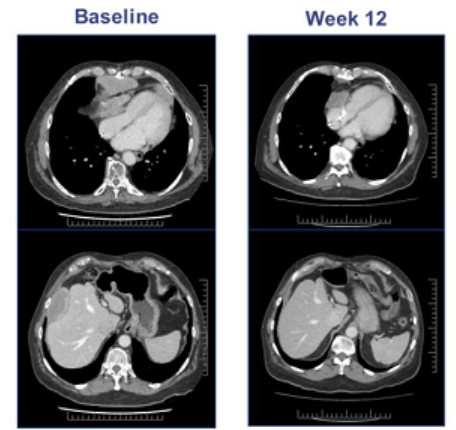

04、疾病控制率90%!ADP-A2M4对多种实体瘤有效

在2020年全球最大肿瘤会议ASCO年会中,一项由美国MD安德森癌症中心公布的新型过继性T细胞疗法,ADP-A2M4的1期试验最新数据引起了轰动。在这项研究中,专门采用针对MAGE-A4癌症抗原的TCR-T技术ADP-A2M4,在多种实体瘤类型,包括滑膜肉瘤,头部肿瘤,宫颈癌和肺癌中均获得了缓解,并且多名患者出现持久反应,这意味着这种新型的基于TCR的新兴技术是未来攻破实体瘤的新希望。

在这项I期临床试验中,共纳入了38名至少接受过三线全身治疗,临床上可以说是没有任何标准治疗方案的极晚期患者,包括恶性程度极高的滑膜肉瘤,卵巢癌,头颈癌,胃癌,粘液样/圆形细胞脂肪肉瘤,非小细胞肺癌,膀胱癌,食道癌和黑色素瘤。

试验结果显示,这些患者在接受ADP-A2M4 T细胞治疗后,产生了强烈的响应。9例患者(23.7%)病情缓解或肿瘤缩小,18例患者(47.4%)病情稳定。

其中,本次试验共入组的16例滑膜肉瘤患者,客观缓解率(ORR)43.8%(7名患者肿瘤缩小),疾病控制率为90%以上(14名患者响应)。

这些患者的中位反应持续时间为28周,中位无进展生存期为20周。

会议上报道了一位67岁的男性晚期滑膜肉瘤患者,MAGE-A4高表达(100% 3),接受9.95*10^9ADP-A2M4 T细胞治疗12周后,最大的肿瘤病灶(155mm)缩小了45%,随着进一步的治疗,肿瘤缩小了71%。

ADP-A2M4疗法用于治疗滑膜肉瘤,已在2019年分别获得FDA授予的再生医学先进疗法称号(RMAT)和治疗软组织肉瘤的孤儿药称号(ODD)。值得振奋的是,基于以上积极数据,该公司预计ADP-A2M4将于2022年在美国上市。